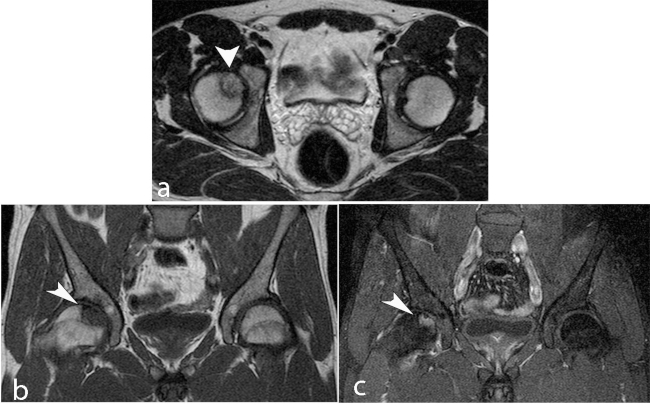

La ON de la cabeza humeral conocida como enfermedad de Hass es la segunda en frecuencia, se desarrolla en la región subcondral, puede provocar colapso del hueso subcondral necrótico, desarrollo de una superficie articular irregular y posterior degeneración de la articulación.

Puede tener varias etiologías: idiopática, secundaria a causas médicas (por fijación quirúrgica o artroscopia), farmacológica o secundaria a un trauma, siendo ésta última la más frecuente. Las fracturas de la cabeza humeral con tres fragmentos pueden desarrollar ON en 3 a 14% de incidencia, mientras que aquellas con cuatro fragmentos, entre 13 y 34%.19

Existe una escala para determinar el grado de severidad de la necrosis mediante hallazgos imagenológicos por RM con el fin de identificar y guiar el tratamiento adecuado, siendo esta la clasificación de Cruess Modificado (►Tabla 4) a partir de la clasificación Ficat y Arlet (►Figs. 9 y 10).20

Hertel describe criterios radiográficos como predictores de isquemia para establecer el compromiso vascular de la cabeza humeral: extensión metafisaria de la cabeza humeral de < 8mm y la disrupción del eje medial > 2mm. Estos hallazgos, en asociación a una fractura del cuello anatómico, presentaron un valor positivo predictivo de 97% para el desarrollo de isquemia.19